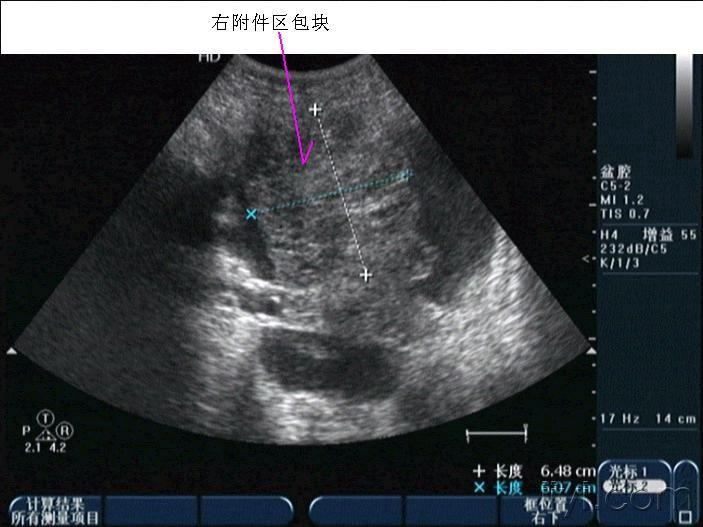

早孕并黄体破裂

晚上房事后腹痛入院,第二天早晨8点多超声所见如下,手术证术为黄体破裂。